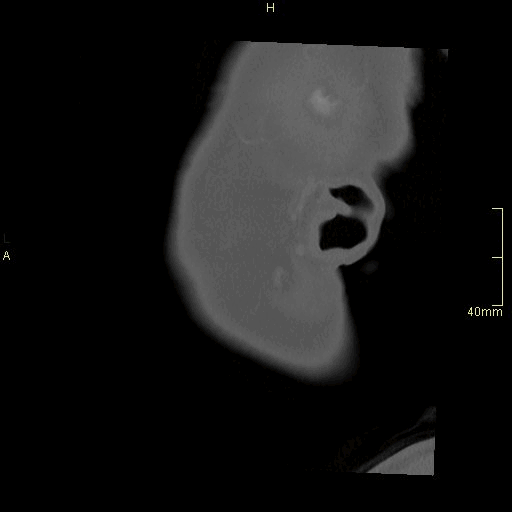

CT Facial Bones/Sinuses Contrast- Soft Tissue window (axial)

CT Facial Bones/Sinuses Contrast- Soft Tissue window (coronal)

CT Facial Bones/Sinuses Contrast- Soft Tissue window (sagittal)

CT Facial Bones/Sinuses Contrast- Bone window (axial)

CT Facial Bones/Sinuses Contrast- Bone window (coronal)

CT Facial Bones/Sinuses Contrast- Bone window (sagittal)